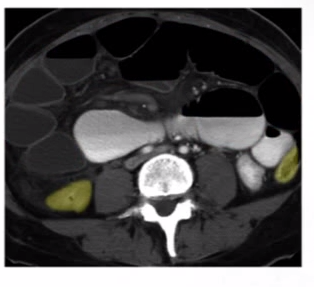

What is this showing…?

SBO 2/2 hernia

-see dilated bowel (blue and yellow) up to rapid transition point, w/ collapsed bowel (red) right after herniated portion of bowel